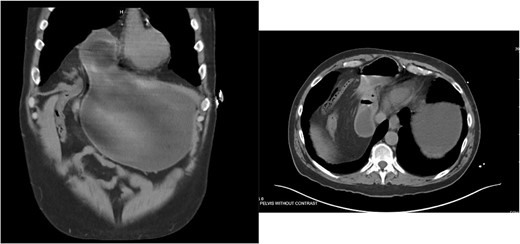

He underwent a CT scan ten months after surgery for flank pain with suspected nephrolithiasis, which demonstrated the successful repair (Fig. 6).